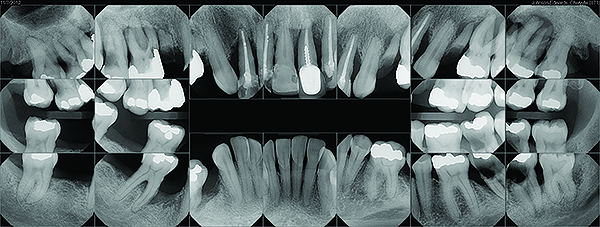

Fig 3. Gross caries and severe periodontitis in a patient presenting with a chief complaint of halitosis.

Figure 3

Fig 4. Periodontal disease in a patient with halitosis.

Figure 4

Clinical and radiographic examinations are essential to diagnose dental pathologies. Carious lesions, defective restorations, or fractured cusps, restorations or teeth (Figure 2 and Figure 3) can be sources of malodor both due to food impaction and foul odor associated with necrotic pulp tissue in cases of severe decay.10 Proper excavation, restorations, and regular follow-up are essential for the successful treatment of these patients. Areas of food impaction should be evaluated for restorations to close the embrasure space. Proper instruction of home care via dental floss and/or interproximal brushes is also required. An individual prone to caries as the source of malodor may also benefit from the adjunctive use of a fluoride-containing mouthrinse or toothpaste.

A rotten egg or cabbage smell is indicative of VSC being the main cause of halitosis. These compounds are usually associated with periodontal disease (Figure 3 and Figure 4) and/or tongue coating. Patients suffering from periodontitis or peri-implantitis require professional periodontal treatment in order to eliminate periodontal pathogens.5 Following a professional scaling and root planing appointment, Gram-negative anaerobic bacteria responsible for causing periodontal disease and producing VSC are reduced.5 This, in turn, encourages repopulation with Gram-positive cocci and bacterial rods that are associated with oral health.